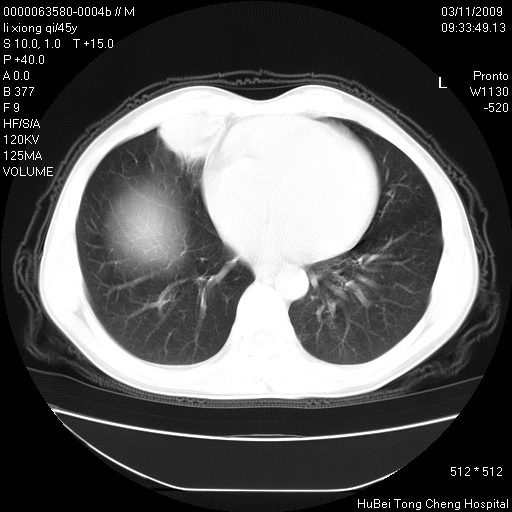

患者 男,45岁。胸痛,咳嗽伴痰中带血1月余。

临床诊断:肺结核?

胸部ct轴位平扫(层厚10mm,螺距1.5,重建间隔10mm),图像如下:

考虑肝癌肺转移